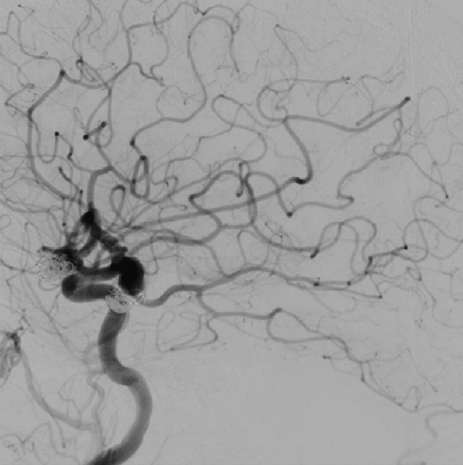

Immediate post-procedure angiography

Post-deployment angiography confirmed clear stent visibility, excellent wall apposition, unobstructed distal vessels and branches, and obvious contrast stagnation within the aneurysm sac—showing a distinct “crescent sign.” The delivery system was then successfully retrieved.

Clear visualization of the stent

Postoperative Outcome

Multiview angiography after the procedure showed optimal wall adherence of the Nuva® stent, with no signs of intracranial hemorrhage or ischemia. The operation concluded successfully.